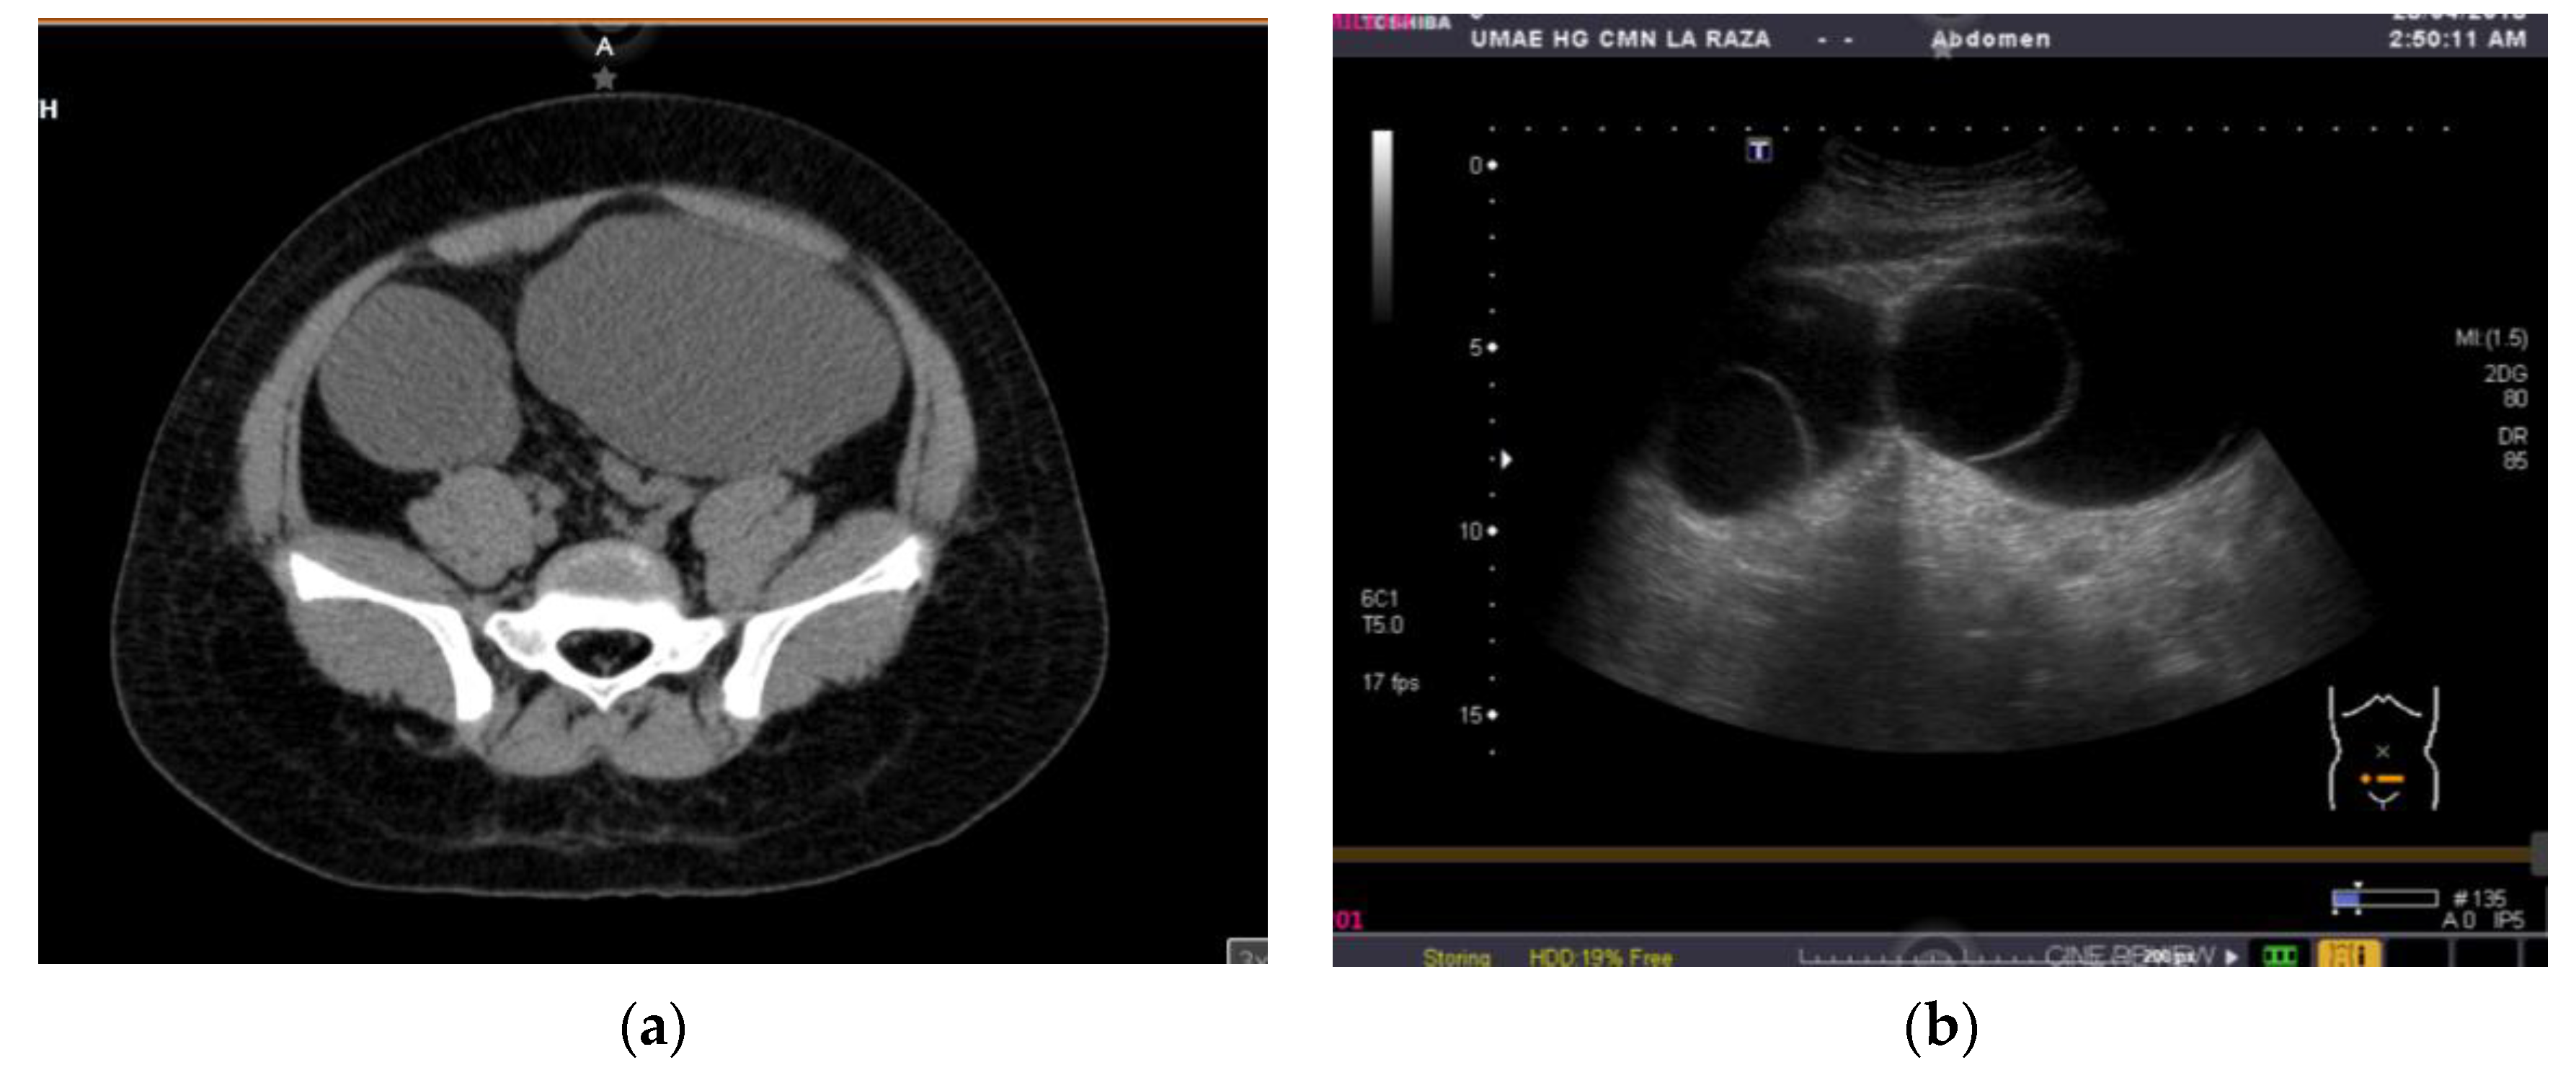

The patient was referred to our hospital, where a second ultrasound found anechoic abdominal lesions with a round, dense material inside. A subsequent CT showed two pelvic lesions of 20 HU, one of 174 cc (right ovary) and the other of 333 cc (left ovary). The left one had a round interior image of 250 HU inside. The radiological diagnosis was adnexal vs. mesenteric cystic tumors (Figure 1a,b). Blood tumor markers were negative (Table 1).

Figure 1. (a) Tomography image from two pelvic tumors; (b) Ultrasound image from a pelvic tumor.